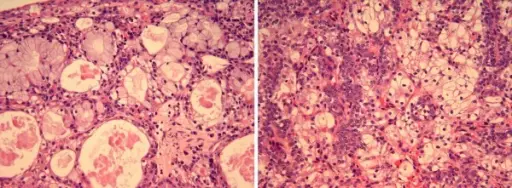

Warthin tumor is a benign cystic tumor with a stroma that resembles a lymph node and many lymphocytes.

Warthin tumor is also known as papillary cystadenoma lymphomatosum.

Warthin tumor is the second most common salivary gland tumor.

Warthin tumor occurs almost invariably in the parotid.